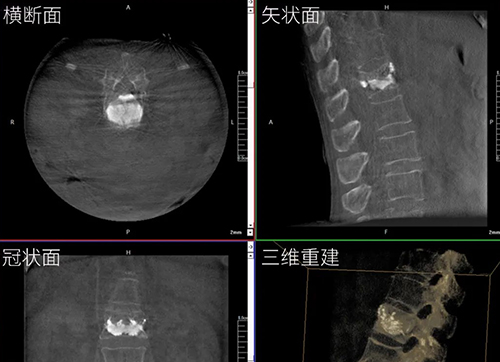

三維C形臂與二維C形臂臨床圖像實時對比

移動式C形臂X射線機有著二維和三維之分,它們都具備透視與攝影功能,能夠為醫生提供術中影像引導。三維C形臂采集的圖像究竟比二維C形臂好在哪?下面我們結合臨床病例的影像來解答!...